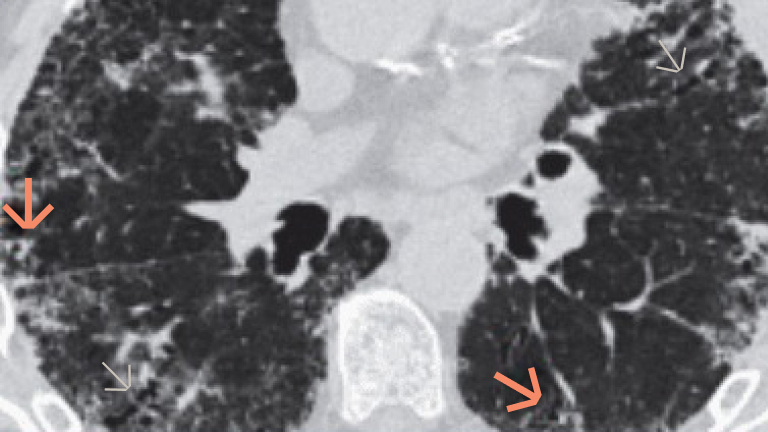

The pathogenesis of fibrotic interstitial lung disease in connective tissue diseases involves a complex interplay of inflammatory and fibrotic processes. Patients with connective tissue diseases (CTDs), such as rheumatoid arthritis, systemic sclerosis and primary Sjogren’s syndrome, develop fibrotic interstitial lung disease (ILD) via common pathogenic processes, irrespective of the underlying diagnosis or trigger. Fibrotic ILD often develops early in the course of a CTD. For example, in a study of systemic sclerosis patients, approximately 24% of systemic sclerosis-associated ILD patients showed an extent of more than 10% pulmonary fibrosis on high-resolution computed tomography at their baseline systemic sclerosis diagnosis. At the cellular level, ILD in CTDs is triggered by repeated tissue injury which induces an inflammatory response, and releases probiotic mediators, including VEGF, PDGF and FGF. These contribute to the recruitment and activation of leukocytes and fibroblasts. Resulting in a complex interplay of inflammatory and fibrotic processes. Activation of leukocytes also produces profibrotic mediators leading to further activation of the fibrotic process with excessive secretion of extracellular matrix. Excess extracellular matrix increases lung tissue stiffness, further activating fibroblasts in a feed-forward loop of self-sustaining progressive pulmonary fibrosis. Pulmonary fibrosis causes irreversible destruction and architectural disruption of the lung tissue. Based on the pathogenesis of fibrotic interstitial lung disease in connective tissue diseases, a new treatment paradigm of CTD-ILDs suggests to not only target inflammation but also fibrosis.